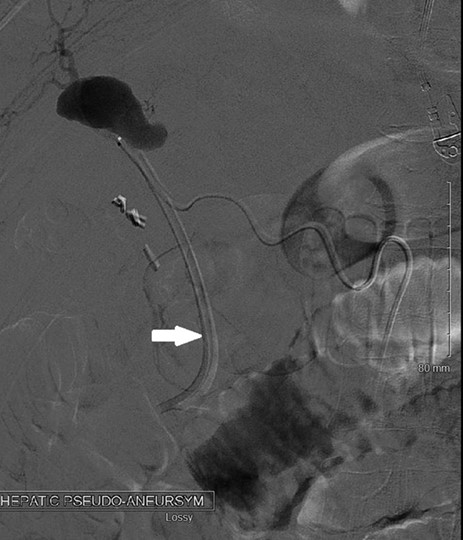

Angiography showing the hepatic artery pseudoaneurysm filling, with the arrow pointing to the catheter used for embolization.